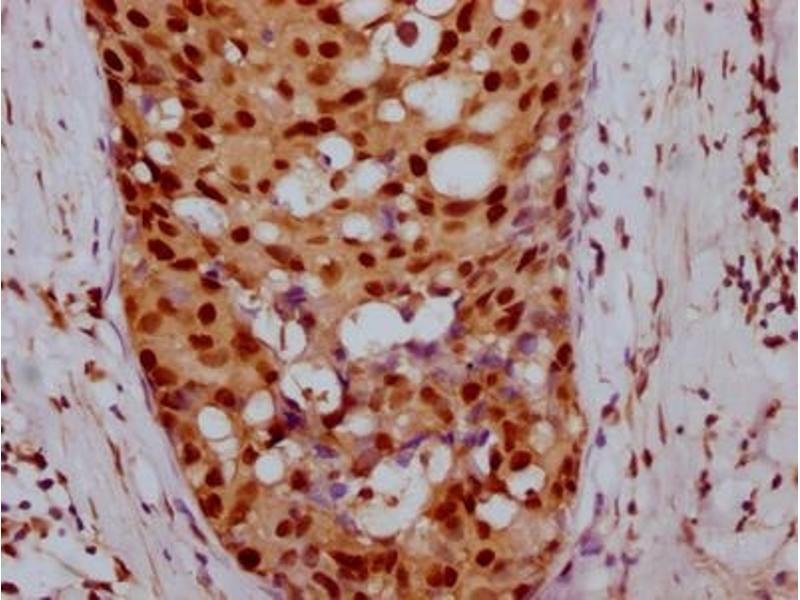

Cyclin E1 抗体

(Cyclin E1 (CCNE1))

CCNE1 适用: 人 IHC 宿主: 兔 Monoclonal 898R unconjugated Recombinant Antibody

产品编号 ABIN7826111

100 μL (More quantities available)